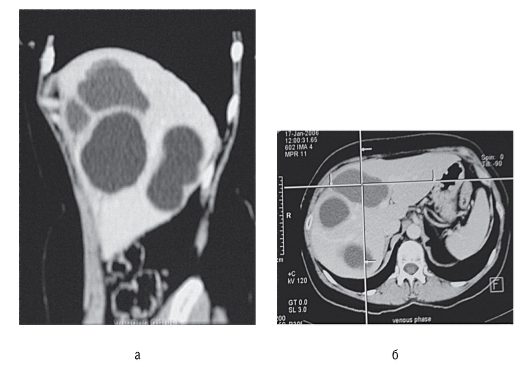

Больной, 53 лет, поступил с жалобами на ноющие боли в верхних отделах живота, усиливающие после еды, похудание. Из анамнеза известно, что 3 года назад перенес острый панкреатит. Злоупотребляет алкоголем. Объективно: пациент пониженного питания, показатели общего клинического и биохимического анализов крови в норме. При УЗИ в проекции головки ПЖ определяется полость (рис. 69) диаметром 45 мм, с однородным жидким содержимым, эхоплотными

стенками до 4 мм, проток ПЖ расширен до 6 мм, ПЖ повышенной эхоплотности, с неровными, но четкими контурами; размеры тела и хвоста ПЖ не изменены. При КТ подтверждено наличие жидкостного образования (рис. 70). При пункционной цистографии выявлено контрастирование протока ПЖ, в полученной жидкости из полости в области головки ПЖ уровень амилазы 2500 ЕД.

Рис. 70. КТ брюшной полости того же больного

Больная, 56 лет. Около года назад возник приступ острых болей в правом подреберье. В экстренном порядке осуществлена надвлагалищная ампутация матки с придатками в связи с разрывом кисты. Серологическая реакция на эхинококкоз «+». Диагноз: эхинококкоз печени. Выполнена эхинококкэктомия из V-VIII сегментов печени с частичным иссечением фиброзной капсулы (рис. 71, 72).

Рис. 71. КТ больной, 56 лет, в 2 проекциях (а, б)